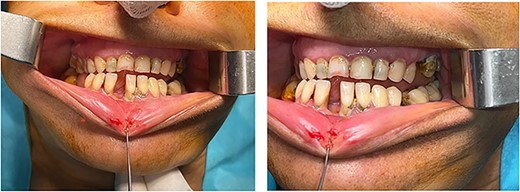

Upon examination, the patient was conscious and stable. The maxillofacial evaluation showed left periorbital edema and ecchymosis, depression of the malar eminence (Fig. 1), tenderness upon palpation of the four malar articulations, a step-off in the lateral orbital rim, and depression of the zygomatic arch. Ophthalmologic exam was normal, and no paresthesia was noted. Intraoral assessment showed restricted mouth opening and an open crossbite (Fig. 2).

(a) Mouth opening; (b) reestablishment of the cheek’s projection.